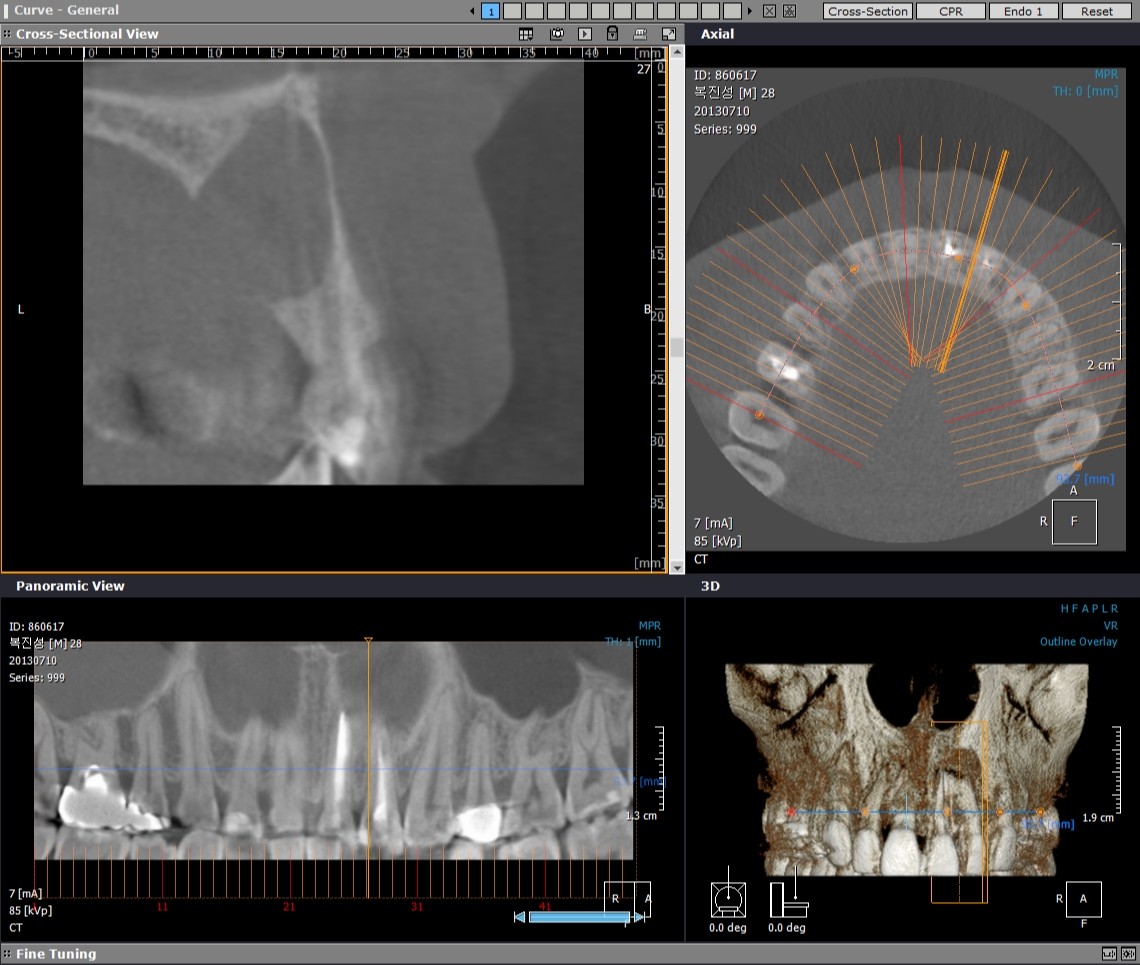

2013-07-15 CT

그런데 신경치료 후에도 염증의 사이즈가 줄어들지 않아서 치근단수술을 진행하기로 하였습니다.  정확한 진단을 하기 위해서 CT를 찍어 보았습니다.